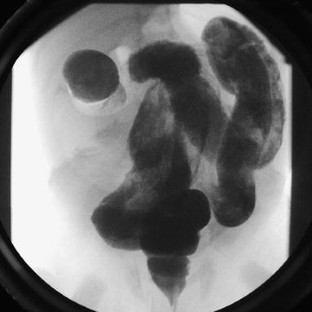

Fig. 2